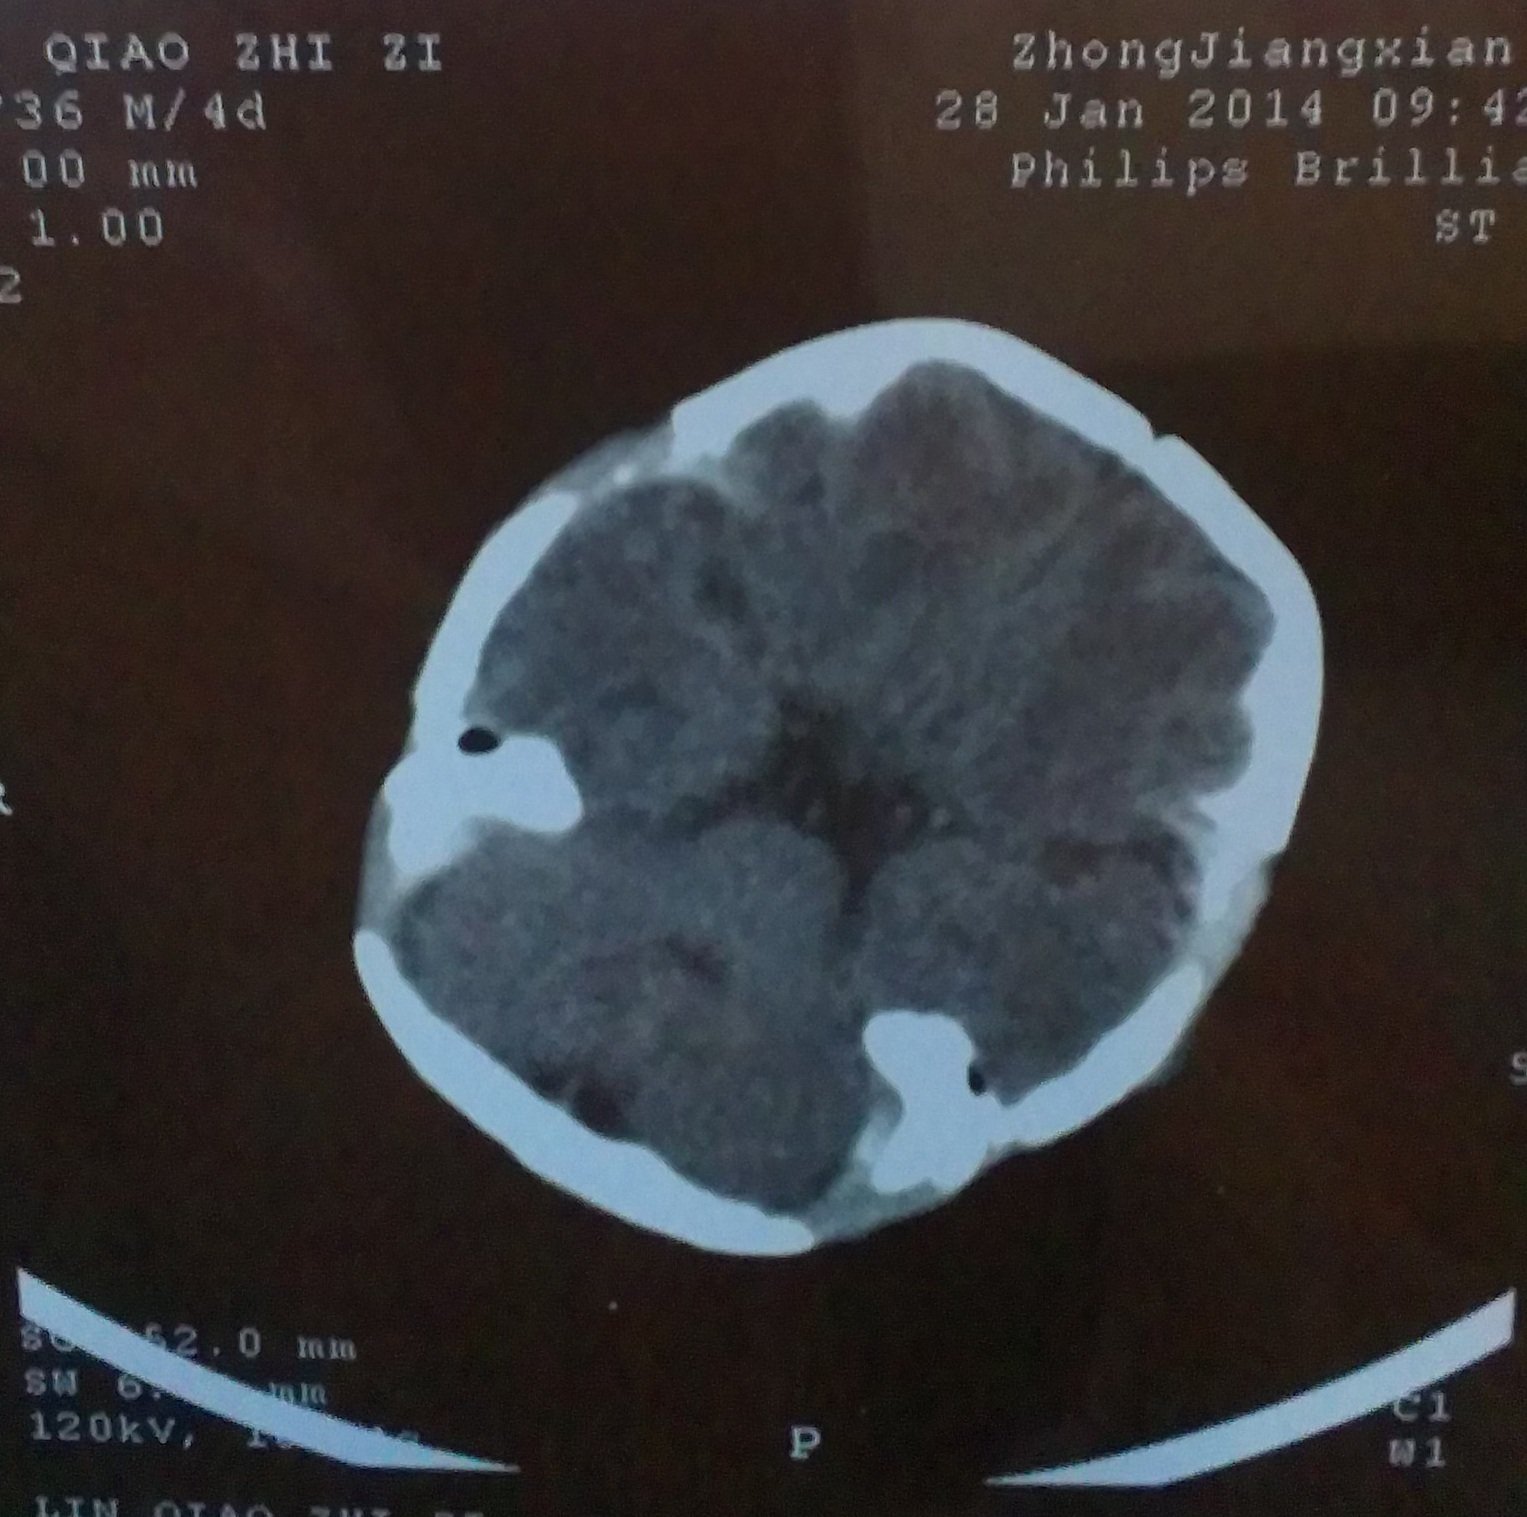

跪求能看懂脑部CT片子的专业人士帮忙,请帮我看一下,我小孩的脑部是什么问题 小孩是36周早产,这是 出生后第四天拍的CT片子,请帮我看一下,脑部有什么问题,严重吗?我应该怎么办,,,不胜感激,,,好人一生平安,感谢。 点击展开 匿名用户 2014-02-25 19:09 为您推荐: 其他回答 你好根据CT上的表现有蛛网膜下腔出血的表现,建议如果小孩子有不爱哭闹或者吃奶不好活动不好等情况及时复查一个颅脑CT或者MRI看看 丑梦月_TNVJ 2014-02-25 22:12 相关问题 宝宝是36周+2的早产儿,年龄25天了,医生要给宝宝照脑部CT,请问这么小照脑部CT 宝宝33周早产,已在保温箱5天了,检查均无问题(除脑部CT),现在每隔3小时吃一次,每次25mL 请问有谁的早产儿脑部发育不成熟用过申捷注射液?对大脑能够发育到什么程度?CT检测:脑部发育欠完善